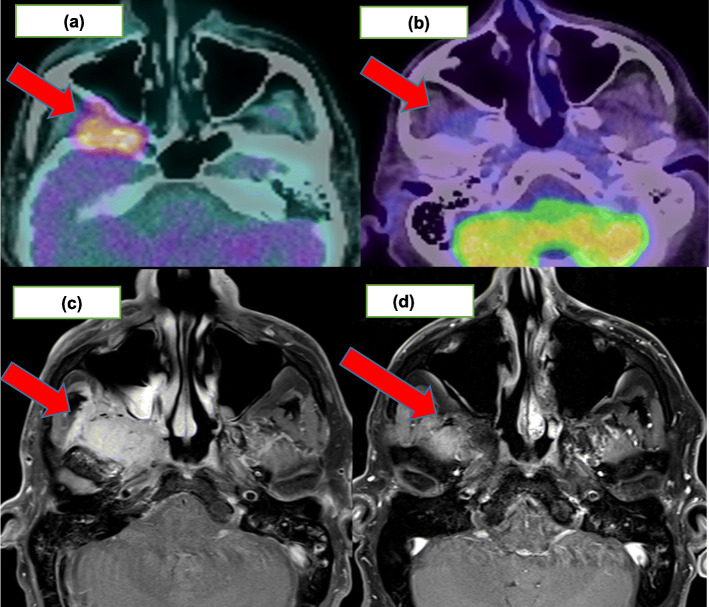

Using FDG-PET, 11 patients achieved a CMR (73% [95%CI:44.9, 92.2%]) of which only one achieved a complete response (CR) on RECIST1.1 assessment. Nine (82%) of these 11 patients had a partial response (PR) on RECIST1.1 for which two examples are shown in Figs. 1 and 2. Response assessments for FDG-PET and RECIST1.1 were concordant for the two patients with progressive disease. Table 2 highlights the imaging responses for this cohort. Cohen’s Kappa value for overall concordance between RECIST1.1 and PERCIST1.0 evaluation was − 0.18.

Fig. 2.

68 year old man with imaging for advanced cutaneous squamous cell carcinoma involving the right skull base, right infratemporal fossa and right trigeminal nerve managed with cemiplimab 350 mg/3-weekly. a demonstrating avid disease at baseline and (b) a CMR post 24 cycles. c demonstrating 41 × 23 mm enhancing mass on baseline MRI and (d) an ongoing RECIST1.1 PR post 24 cycles